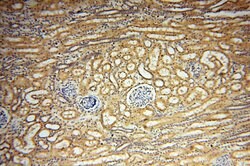

SYK Rabbit anti-Human, Mouse, Rat, Polyclonal, Proteintech

This gene encodes a member of the family of non-receptor type Tyr protein kinases. This protein is widely expressed in hematopoietic cells and is involved in coupling activated immunoreceptors to downstream signaling events that mediate diverse cellular responses, including proliferation, differentiation, and phagocytosis. It is thought to be a modulator of epithelial cell growth and a potential tumor suppressor in human breast carcinomas. Alternatively spliced transcript variants encoding different isoforms have been found for this gene.Specifications

| Immunohistochemistry (Paraffin) | |